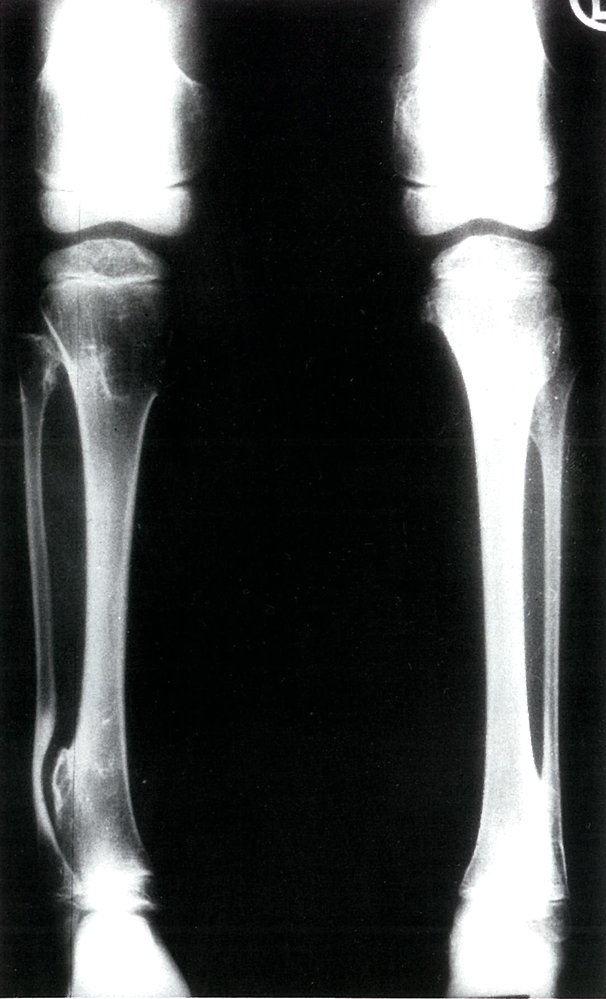

Giant-cell tumor (osteoclastoma)

• Tumor arising from giant cells of the bone marrow

• Peak incidence: 20–40 years

• Epiphysis of long bones (usually around the knee)

• Local pain and swelling

• Pathological fractures

• X-ray: multicystic osteolytic lesions (soap-bubble appearance)

• Histopathology: multinucleated giant cells and mononuclear, RANKL-expressing cells

• Locally aggressive tumor

• Risk of malignant degeneration increases with age.

• Description: benign but locally aggressive tumor composed of giant cells that arise from the bone marrow [1]

• Epidemiology: peak incidence between 20 and 40 years

• Clinical features

• Found in the epiphysis or metaphysis of long bones (especially knee region)

• Limited range of motion

• Diagnostics

• Histopathology

• Mononuclear, RANKL-expressing cells (neoplastic)

• Multinucleated giant cells (are reactive and resemble osteoclasts)

• Treatment: curettage and bone grafting or en-bloc resection to minimize recurrence rate

• Prognosis: risk of malignant degeneration increases with age; may spread to the lungs